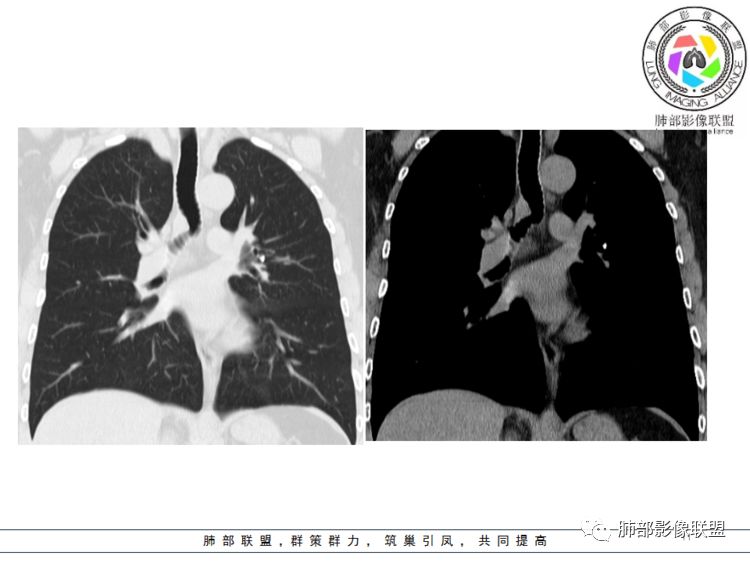

病灶跨气管壁内外,主体在外;边界清,密度均匀

明显看到气管壁软骨受压内移

局部是撑开的,就是说软骨不是破坏

表面隆起,有小斑点

无症状;倾向于良性,平滑肌瘤?神经源性肿瘤?不除外其他

南边分析:针对本例,病灶跨气管壁内外生长,常规跨内外的有:恶性肿瘤为主,其次就是神经源性、平滑肌瘤;常规的思维:跨内外就要看结构的变化气管的优势在于软骨相对密度高,而且成C型

我们如何分析这个病例?冠状位:软骨密度稍高;病灶区软骨部分区域不连续,外围连续,提示病灶推移为主,不是破坏为主;如果破坏,应该这些软骨显示不清,移位不明显

病灶从软骨见推移开,跨内外,因此定在良性。恶性是侵犯,破坏为主,如果破坏,应该这些软骨显示不清,移位不明显,不是推移为主这例病变定在良性,我们就要考虑:1、软骨之间的平滑肌来源;2、神经源性

病例小结      气管神经鞘瘤属于罕见的气管良性肿瘤,一般气管良性肿瘤或腔内或腔外生长的结节样改变,恶性肿瘤呈腔内外生长,但本例肿块向腔外生长,呈“冰山样改变”,即肿瘤的腔内部分较小而腔外部分较大,无周围组织侵犯。因此肿瘤腔内外生成不能作为鉴别气管良恶性肿块的绝对依据。        因此冠(矢)状位多平面观察、软骨是否破坏、气管壁有无增厚等细节观察,对于鉴别气管肿块良恶性有重要的参考性。

1.气管隆凸上右前壁不规则结节影,部分突入腔内,南边老师观察有推挤软骨环“破土而出”的形态特征。注意没有沿气管粘膜表面生长蔓延的生物学行为。

2.影像学病灶占据腔内外,但病灶边缘十分清楚。这点倾向良性。